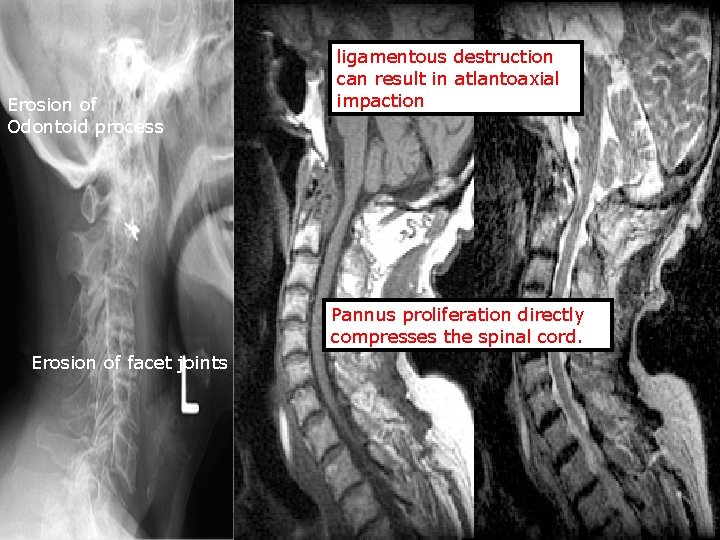

Erosion of Odontoid process ligamentous destruction can result in atlantoaxial impaction Pannus proliferation directly compresses the spinal cord. Erosion of facet joints